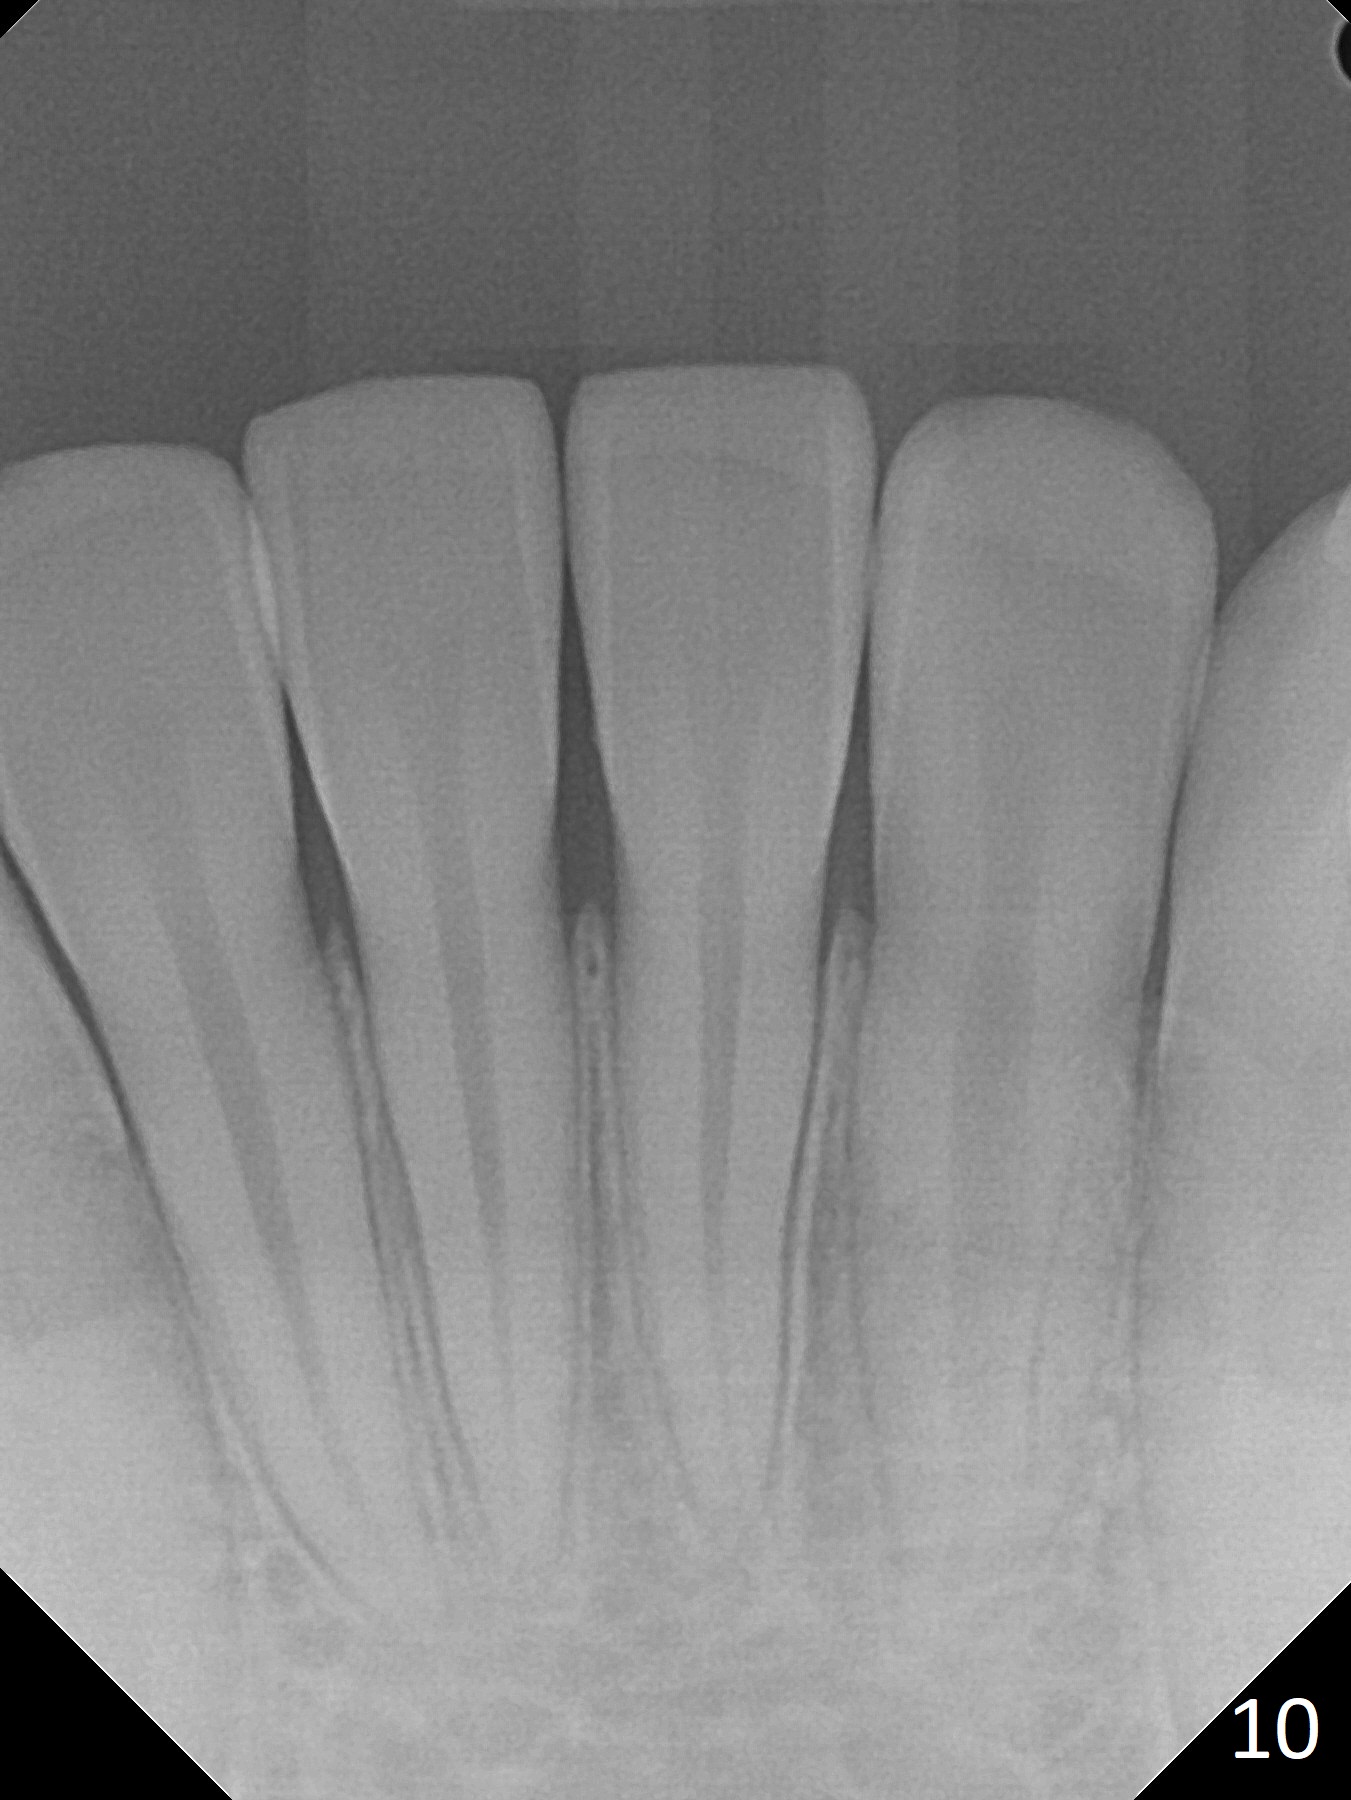

Shallow Overbite

A 12-year-old man has mild lip protrusion (Fig.1,6,7). Orthodontics will be conducted without extraction. Unlike his elder brother, the overbite is shallow. With anterior bracket differential (4-4-5 mm) and mild bimaxillary protrusion, open bite will be created? Or 4-4-4.5mm scheme should be adopted to avoid open bite?